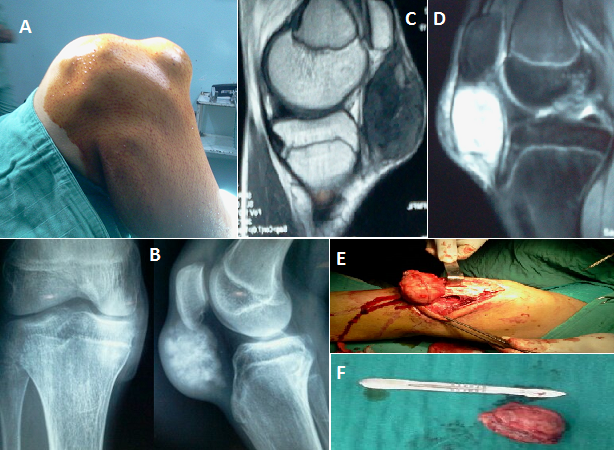

Les chondromes para-articulaires sont des tumeurs cartilagineuses bénignes qui se développent près des articulations. L'étiologie de cette lésion n'est pas bien connue, mais elle résulte probablement de traumatismes répétés qui peuvent être l'origine d'une métaplasie de cellules mésenchymateuses extra-synoviales. Nous décrivons des images cliniques, paracliniques et per opératoires d'un chondrome du genou droit chez un jeune patient de 30 ans. Le patient avait consulté pour une masse douloureuse infra-patellaire du genou droit évoluant lentement sans notion de traumatisme ni de signes inflammatoires. Les radiographies standards ont montré une image infra-patellaire de grande taille mais bien limitée en regard du tendon rotulien, avec beaucoup de calcifications évoquant sa nature cartilagineuse. L'IRM a confirmé cette lésion tumorale accolée à la face interne du tendon rotulien refoulé en dehors en hypo-signal en T1 et en hyper-signal en T2, sans anomalies osseuses au niveau du tibia et du fémur et sans lésions cartilagineuses ni ménisco-ligamentaires. Il a été opté pour une résection de cette lésion ; elle a été réalisée sans difficulté par un abord para-patellaire médial, qui a montré une masse faisant partie de la masse adipeuse infra-patellaire, faiblement adhérente au tendon rotulien, elle a pu en être décollée sans difficulté et sans lésion tendineuse. L'examen anatomo-pathologique a montré la nature cartilagineuse de la lésion. En postopératoire, le patient a récupéré complètement la mobilité du genou après 2 mois de rééducation. Il est resté asymptomatique depuis 2 ans au dernier contrôle.